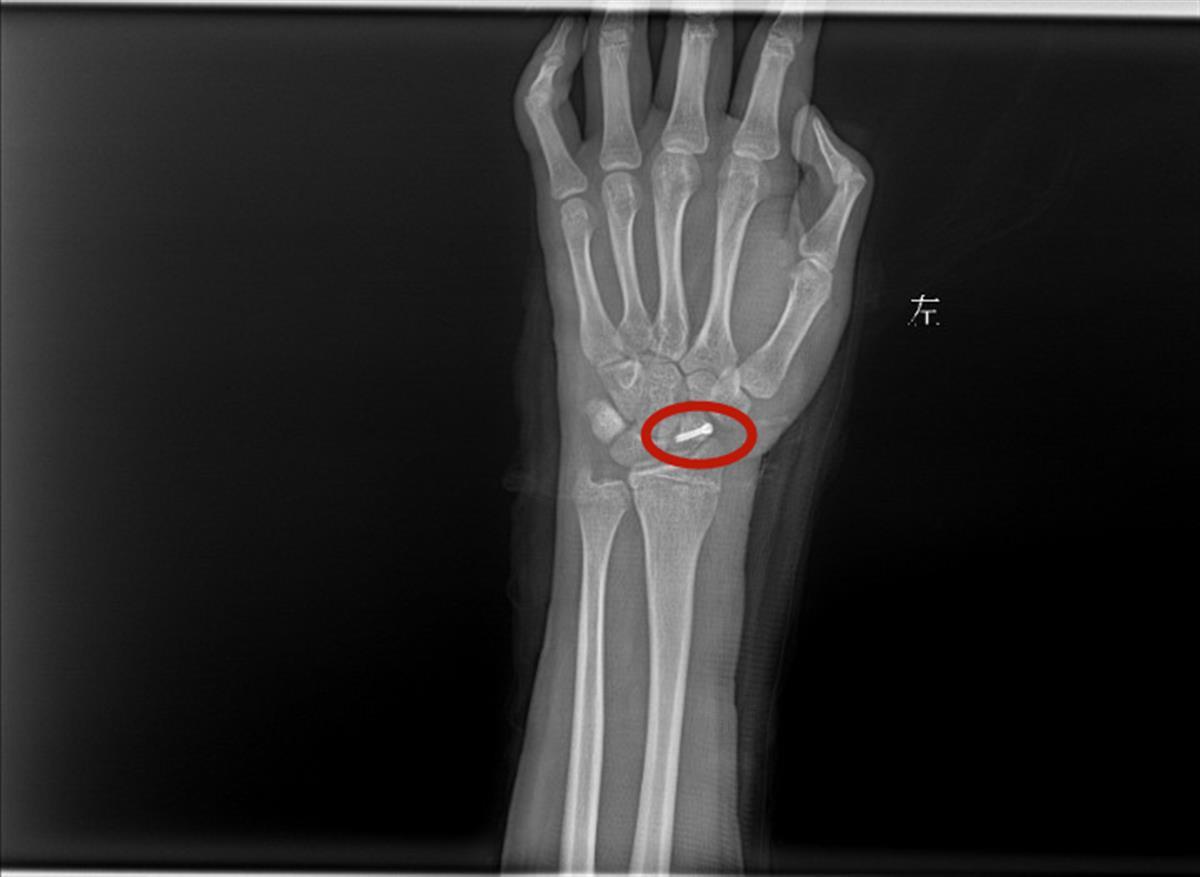

手腕骨折处

接诊的小儿骨科副主任医师李明静介绍,从东东受伤初期的片子来看,骨折处没有明显移位,只需采取石膏固定治疗。一般来说,7-10天最容易发生骨折移位,家长却在这个时间点擅作主张帮孩子拆除了石膏,导致了孩子骨折错位。目前,东东已进行了舟状骨骨折切开复位内固定术,恢复情况较好。